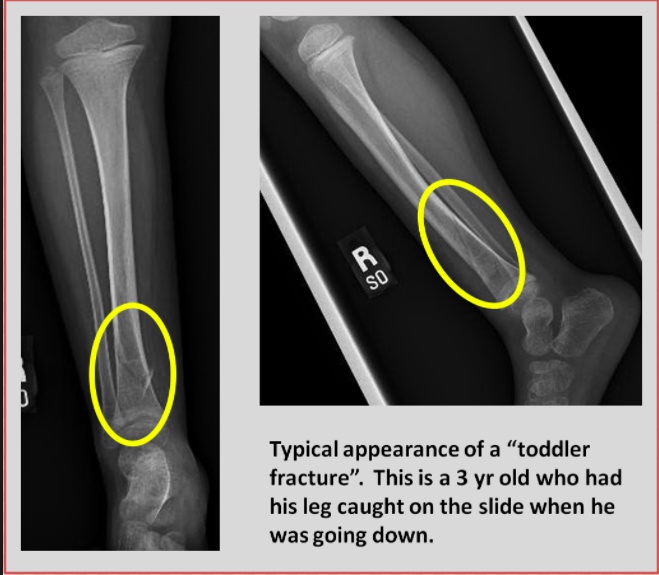

Toddler

A toddler’s fracture is a nondisplaced spiral fracture of the distal tibial metaphysis.

The injury often occurs after a seemingly harmless twist or fall and is often unwitnessed. These fractures will often be presented in a question in regards to worrying about child abuse.

These fractures are most commonly seen in children 1-4 years of age.

The classic symptom of a toddler’s fracture is refusal to bear weight, which can manifest as pulling up the affected extremity or florid display of protest.

The AP and lateral x-ray views of the tibia-fibula may show a nondisplaced spiral fracture of the distal tibial metaphysis. An oblique view is often helpful because the fracture line may be visible in only 1 of the 3 views.

The treatment of a toddler's fracture involves the use of an above-knee cast for approximately 3 weeks.